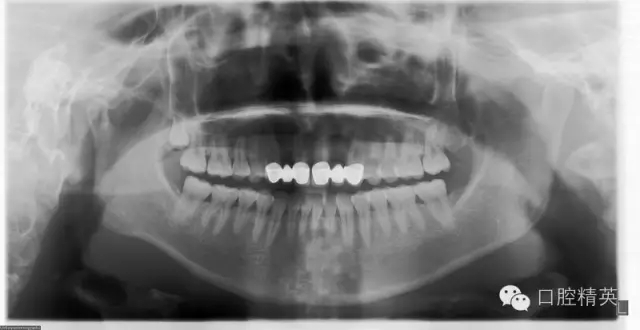

檢查:12及22缺失,13、12、11固定修復(fù)體,21、22、23固定修復(fù)體,11、13、21、23修復(fù)體邊緣不密合,修復(fù)體顏色偏黃,叩痛(—),不松動(dòng),13、23牙齦退縮,11、13、21、23牙齦發(fā)暗,覆牙合覆蓋關(guān)系大致正常??谇恍l(wèi)生狀況尚可。X線片示13、11、21及23牙根長度可,根尖區(qū)無明顯病變,牙槽骨無明顯吸收。12、22缺失。